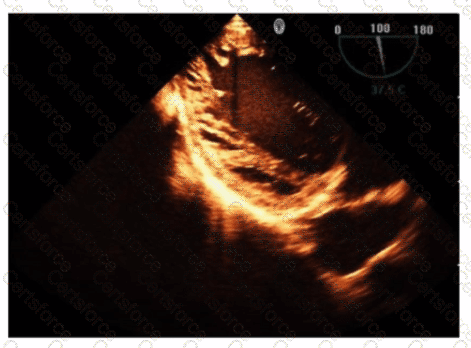

Which pathology is consistent with the left ventricular strain pattern shown in this image?